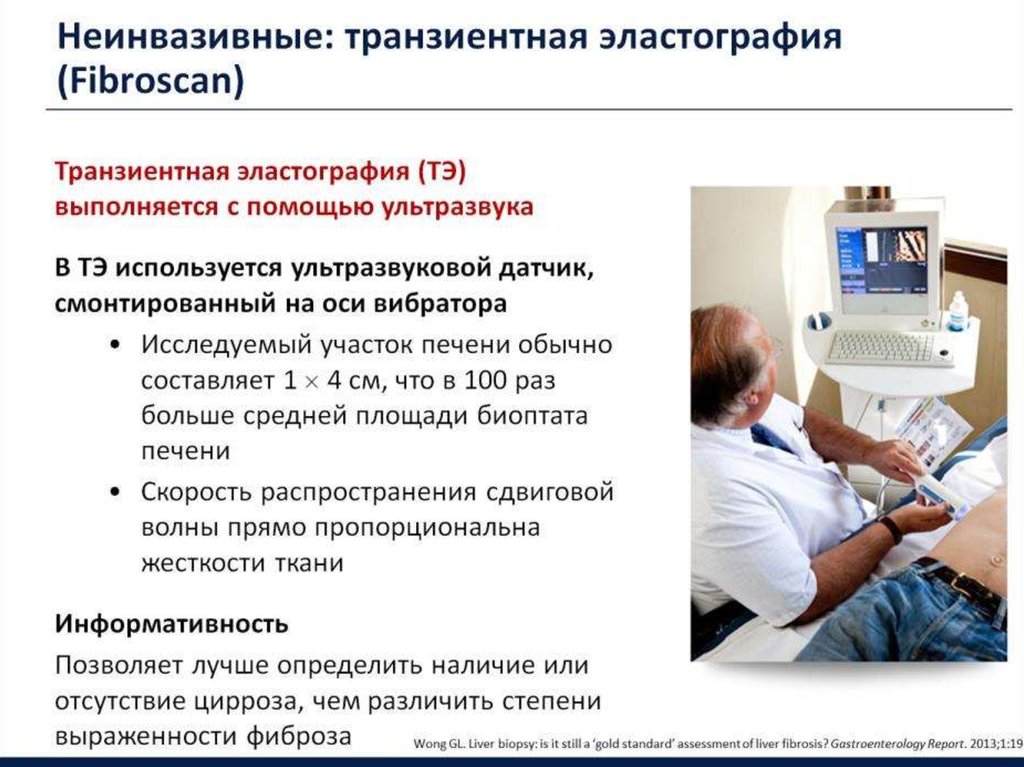

Эластометрия брюшной полости – это современный метод диагностики, который позволяет оценить состояние тканей органов в брюшной полости с помощью ультразвуковых волн. Это исследование помогает выявить различные заболевания на ранних стадиях, таких как цирроз печени, фиброз, воспалительные процессы и другие патологии, что способствует своевременному назначению эффективного лечения.

Эластометрия печени. Что выбрать: фиброскан или УЗИ?

Обратите внимание, что эластометрия безопасна и безболезненна, не требует инвазивных процедур и позволяет получить данные без риска для здоровья.